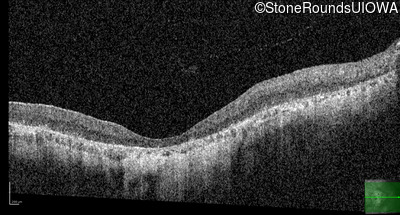

OD

OS

1/200 sc

Age at visit:

76 years

OCT Stack